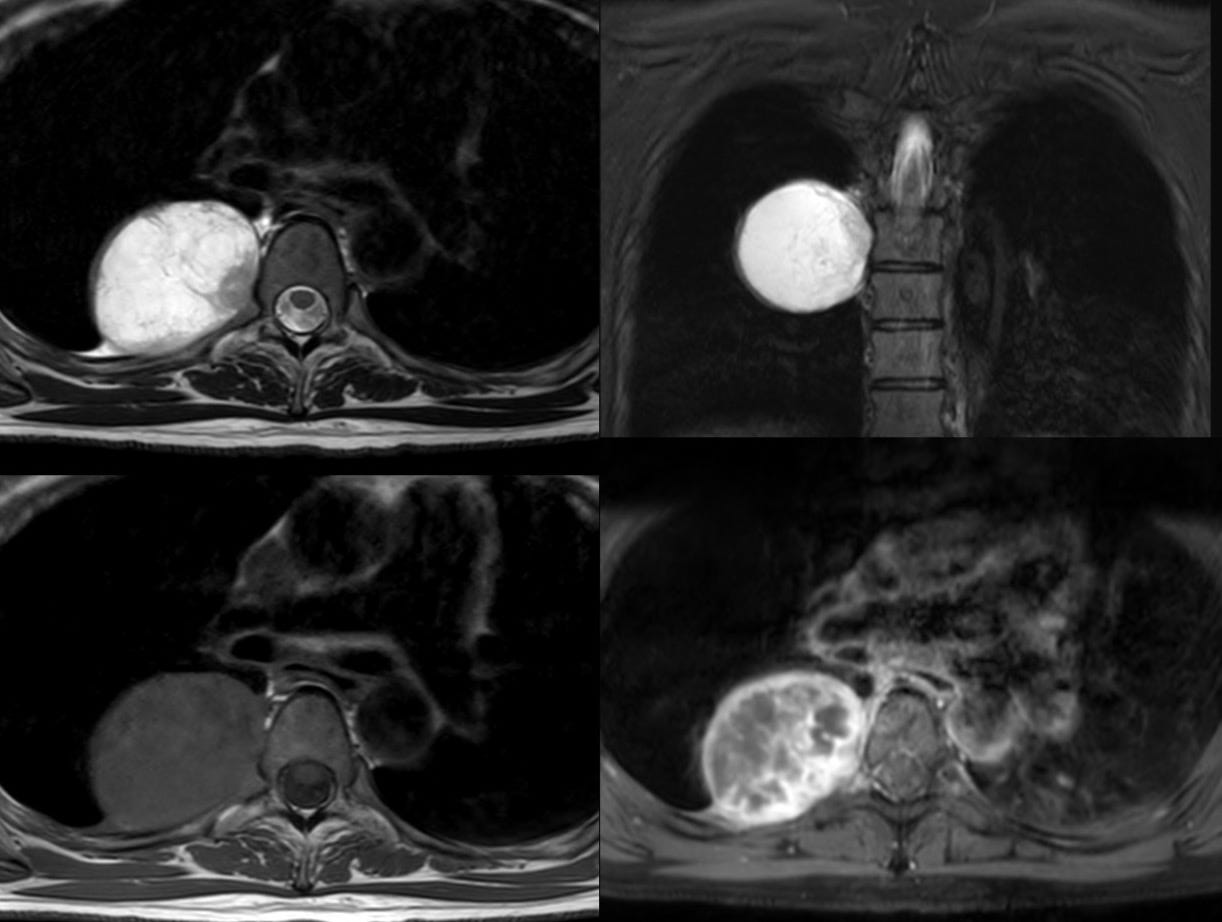

Case 23: An Incidental Posterior Mediastinal Mass

A 39-years old was found to have a mass in the chest on a CT chest done for COVID-19.

What is the likely diagnosis?